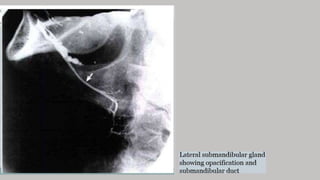

Filming of SM

Inferior superior

-Elevate the patient's thorax on

several firm pillows.

- Place the film in the mouth with the

long axis directed transversely.

- Central ray perpendicular to the

plane of the film

Contd..

• submandibular and sublingual

glands. Calcification (arrow) is

seen in the sublingual region.

• Center the IR to the inferior margin

of the angle of the mandible.

• Adjust the patient's head in a true

lateral position

• depressing the floor of the mouth

to displace the submandibular

gland below the mandible

• Neck should be hyper extended so

that the submandibular gland is

projected below the mandible